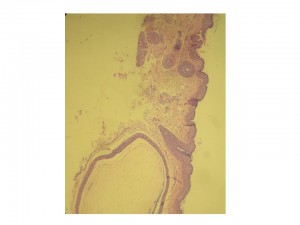

Foto Nº 4. Panorámica: epidermis con redes de crestas elongadas y regulares; ortoqueratosis en cesta. A nivel de la dermis se visualiza una formación de aspecto quístico.

Foto Nº 5. A nivel de la dermis se observa una formación quística revestida por epitelio pavimentoso y presencia de material laminar en su interior.

En la histología se observan quistes revestidos por un número escaso de células escamosas aplanadas derivadas del infundíbulo de los folículos pilosos que contienen en su interior queratina ortoqueratósica. Se suele observar un infiltrado inflamatorio dérmico a predominio linfocitario. (Fotos 4 y 5).